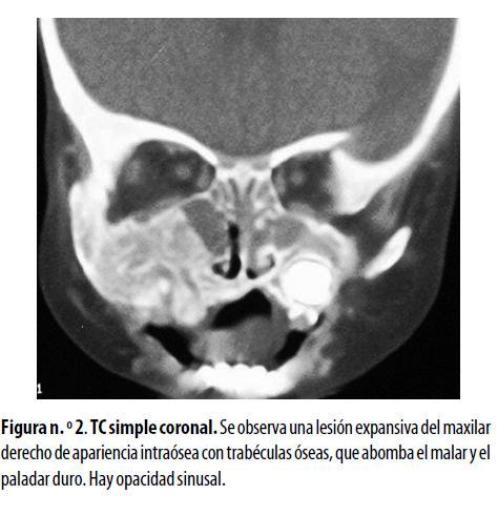

La TC de los senos paranasales mostró una lesión mixta de tejido blando con trabéculas óseas engrosadas, ligeramente expansiva, que afectaba el malar y el maxilar derechos y el paladar duro, pero sin destrucción ósea. Había contacto íntimo con las raíces dentarias pero no lesión subcutánea. Se observó engrosamiento de la mucosa de los senos maxilares y las celdillas etmoidales estaban ocupadas por material con densidad de tejido blando. Se observó también aumento bilateral de los tejidos blandos intranasales (figura n.º 2) . En una biopsia inicial del maxilar derecho se diagnosticó linfoma de Burkitt; se inició quimioterapia pero la respuesta fue mala; requirió varias hospitalizaciones por cuadros de agranulocitosis y síndromes febriles. Otro estudio histopatológico mostró múltiples espículas óseas con áreas necróticas y algunos fragmentos de tejido blando como músculo y tejido conectivo. El estudio inmunohistoquímico reveló la existencia de un SG. Se cambió el esquema de quimioterapia, lo que fue seguido de franca mejoría clínica y disminución del tamaño de la lesión.